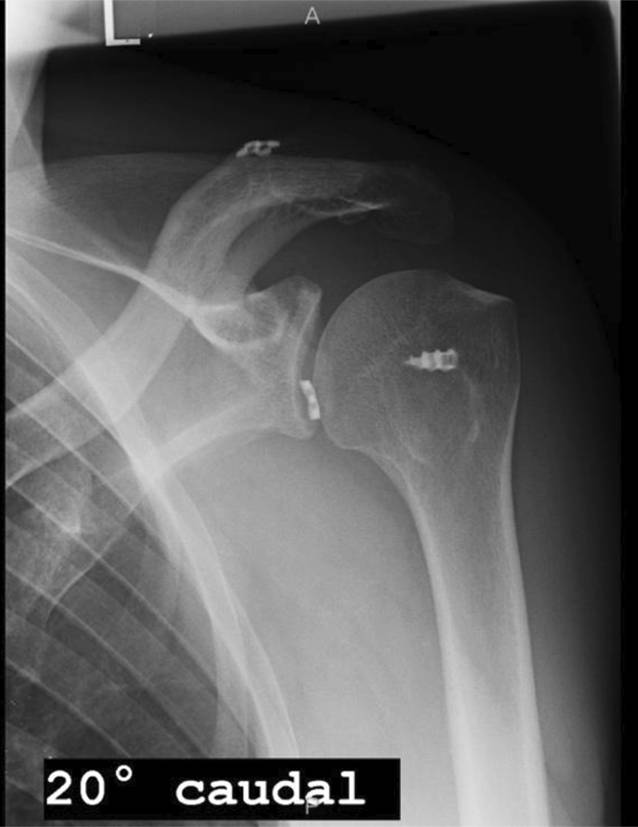

In der durchgeführten radiologischen Bildgebung stellte sich eine chronische ACG-Instabilität mit einem erhöhten CC-Abstand dar. Es imponierte ein nach intraartikulär disloziertes inferiores DogBone-Plättchen (Abb. 2). In der Magnetresonanztomographie (MRT) zeigten sich eine intakte Rotatorenmanschette sowie Knorpelschäden am Humerus im Sinne einer beginnenden Omarthrose.

Abb. 2

Röntgenaufnahme Schulter links a.‑p. 2024: intraartikulär dislozierter inferiorer Button

In Zusammenschau der klinischen und radiologischen Befunde kann die Diagnose einer asymptomatischen chronischen ACG-Instabilität mit partiellem Repositionsverlust links sowie ein nach intraartikulär dislozierter DogBone-Button gestellt werden.